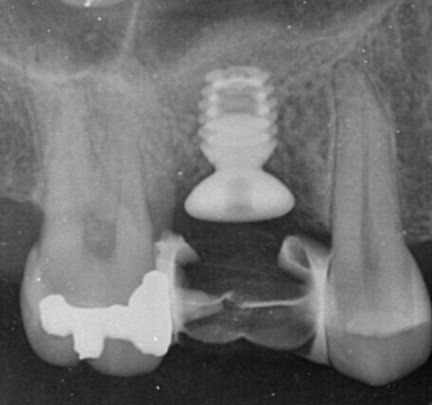

Servizi di implantologia

Per implantologia s'intende l'insieme di tecniche chirurgiche e protesiche volte a riabilitare funzionalmente un paziente affetto da mancanza totale o parziale dei denti, mediante l'utilizzo di impianti dentali, dispositivi inseriti chirurgicamente nell'osso mandibolare o mascellare, atti a permettere la connessione di protesi, fisse o mobili.

Nel corso degli anni la scelta del nostro studio si è progressivamente orientata sull'uso della metodica implantare a connessione conometrica pura, la quale offre una notevole versatilità d'impiego. Ampliando le possibilità chirurgiche e riducendo il rischio di contatto con strutture vitali, queste soluzioni ci permettono di trattare un maggior numero di pazienti affetti da carenza di osso, garantendo comunque un'elevata osteointegrazione. Inoltre semplificano la parte protesica, data l'assenza di connessioni a vite e l'uso di cementi.

prima e dopo...